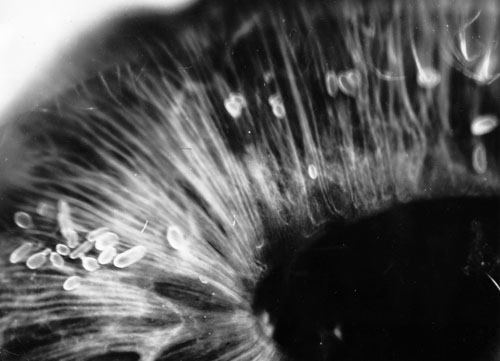

"Ant-Eggs" on the surface of the iris in an aphakic eye. The photography is from the original examination [5] in December 1965 of individual II:6 who carries the L11S mutation.